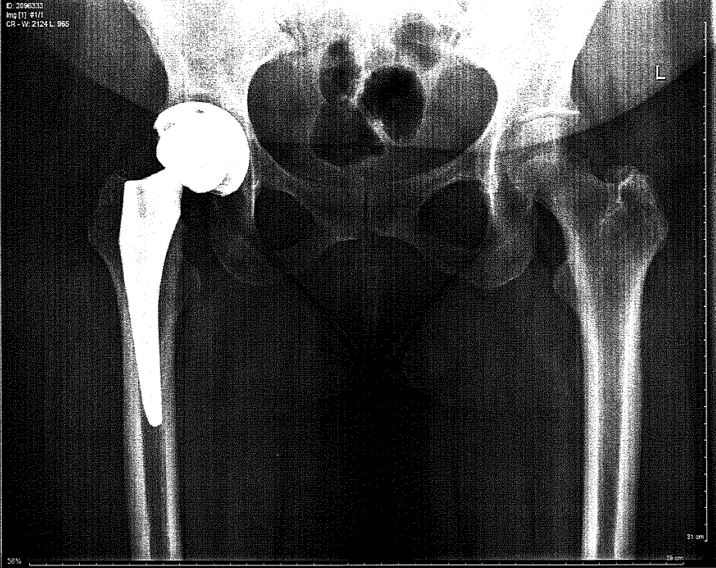

She is referred for a surgical consultation.  An anterior approach hip replacement is performed.

The advantage to this hip replacement approach is that it has a smaller incision, reduced scarring, and faster recovery time because it exposes the hip without detaching muscles or tendons from the bone.